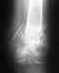

Кость срастается плохо потому, что в реззльтате травм и открытых операций нарушено кровоснабжение концов отломков, повреждена скелетогенная ткань. Несращение малоберцовой кости на результат не влияет. Чтобы не было рецидивов, лучше фиксирвовать не пластиной. а внутрикостным стержнем с блокированием винтами.